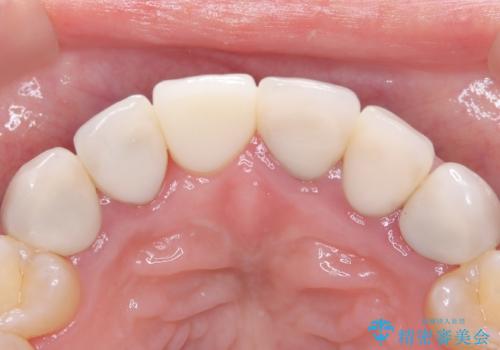

今回の治療では、まず原因となっていた前歯を慎重に抜歯し、その直後にインプラントを埋入しました。抜歯即時埋入は、歯を失うのとほぼ同時に新しい歯の土台を確保できるため、骨の吸収を防ぎ、仕上がりの美しさを保つ上で非常に有効です。また、治療当日に仮歯を装着することで、歯がない期間をなくし、患者様の精神的なご負担にも配慮しました。最終的に、周囲の歯と調和したオーダーメイドのセラミッククラウンを装着。機能性だけでなく、天然歯と見分けがつかないほどの自然で美しい前歯を取り戻していただけました。